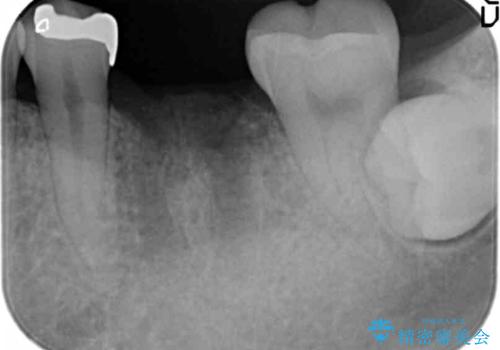

- 銀歯が揺れる、噛むと痛い、と治療を希望され来院されました。

銀歯・レジンコアを除去したところ、薄い残存歯質に亀裂が入り、保存が難しい状況が認められました。